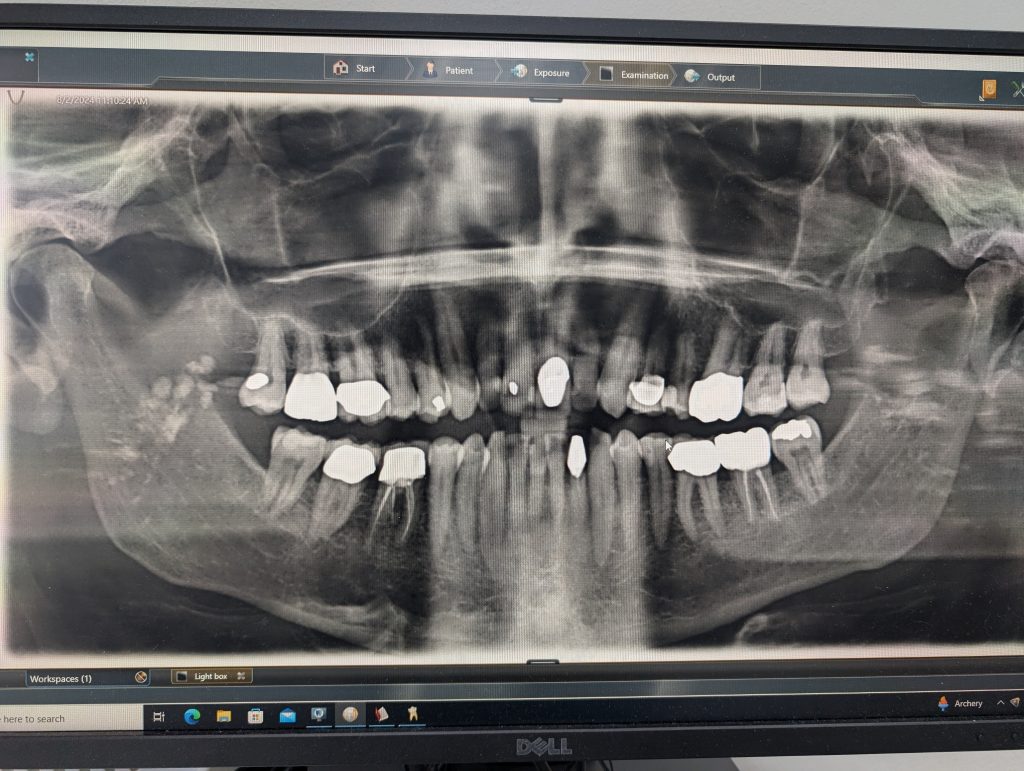

Something you don’t want to hear from your dentist: this x-ray shows some “areas of concern”. She was not talking about my beautiful constellation of 8 crowns, rather the scarry blobs in the jaws:

She referred me to an oral surgeon who thankfully diagnosed them as calcified tonsil stones. He suggested I de-tonsilize, but I’m leaning to keeping them for now.